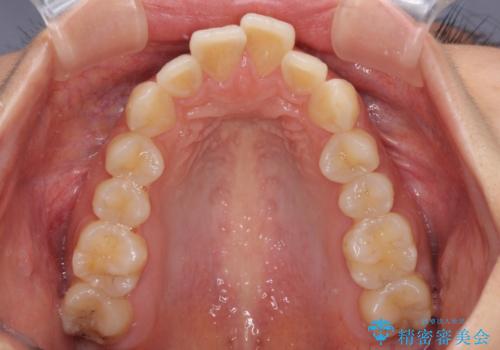

- 前歯の突出感を気にして来院された患者様です。

左右ともに奥歯の咬み合わせが上顎前突となっており、上顎前歯が飛び出している状態でした。

奥歯の咬み合わせ改善が必要であるため、マウスピース矯正より確実に達成のできるワイヤー矯正にて治療を行うこととしました。

奥歯の咬み合わせはしっかりと改善され、前歯の突出感も改善されました。